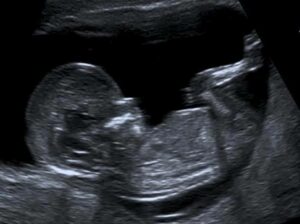

Myome – Bei einem Myom handelt es sich um überschüssiges Muskelgewebe [Muskeltumor]. Dieser kann nach außen oder nach innen in die Gebärmutter wachsen. Wenn unser Körper ein Myom nach innen erkennt, ist das befruchtete Ei [welches mittlerweile ein großer Zellhaufen ist] verwirrt, da es glaubt das Kinderzimmer ist bereits besetzt. Somit ist die Einnistung erschwert. Wenn ein Myom nach außen wächst, sucht es sich den Weg des geringsten Widerstandes, drückt auf andere umliegenden Organe und beeinträchtigt somit deren Beweglichkeit und Funktion.